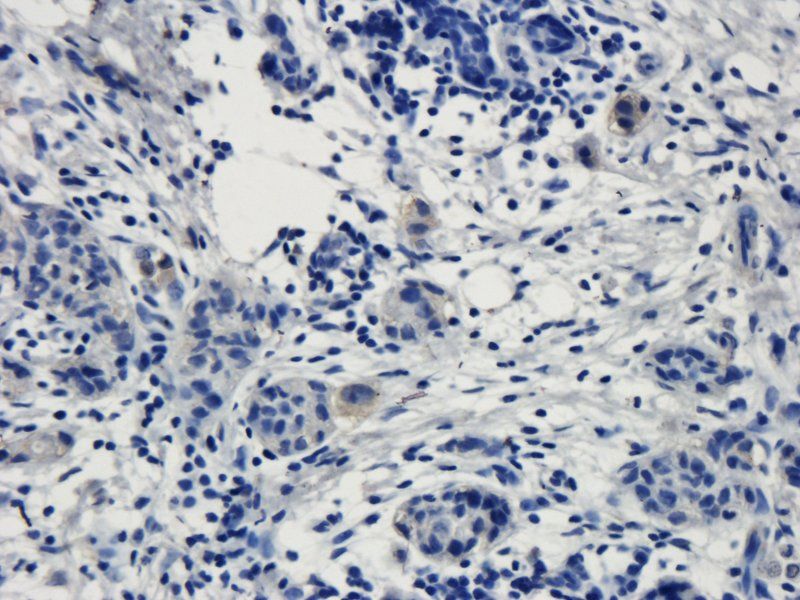

Immunohistochemical staining of human colon cancer using TRPV1 antibody